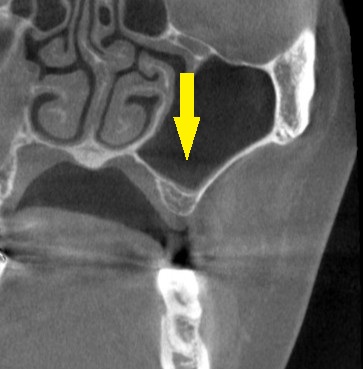

CTを撮影してみると、方向によっては、骨がありそうに見えますが、やはり十分な骨量とはいえませんでした。

ある程度の骨はありますので、ワイドインプラントを用いて、人工骨は使用せず、骨造成も行わないで、インプランント埋入が可能であると説明させていただきました。

ご納得いただけましたので、本日、ワイドショートインプラント、直径5.0mm、長さ7mmのインプラントを埋入しました。

下の写真、2段目が手術前のCT、3段目が手術後のCTです。